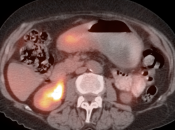

• The utility of PET/CT lies in its assessment of regional nodes and distant metastatic disease.

• Distant Disease: Most commonly to the liver, peritoneum, lung and bone.